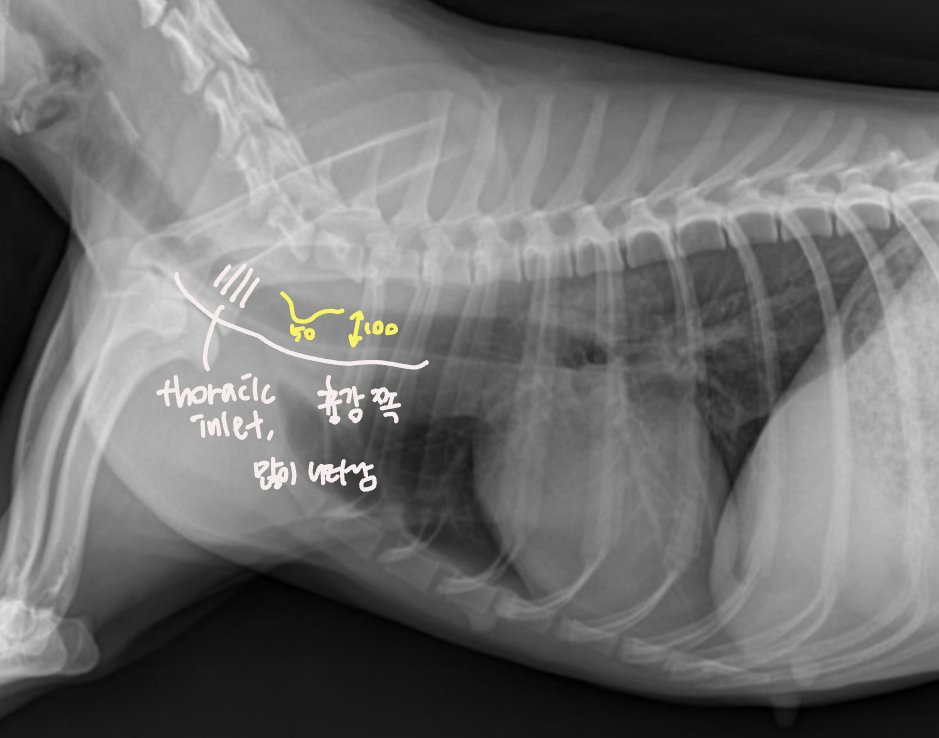

Tracheal diameter ์ฌ๋ ๋ฒ๋ฒ

- Thoracic inlet๊ณผ์ ๋น์จ๋ก ๋ํ๋ธ๋ค.

![]() | - T1์ ๋๋ถ๋ถ์์, 1๋ฒ sternum์ ๊ฐ์ฅ ์ค๋ชฉํ ๋ถ๋ถ (Thoracic inlet)์ ์ ์ผ๋ก ์๊ณ ๊ธธ์ด๋ฅผ ์ฐ๋ค. - Trachea์ ๊ธธ์ด๋ฅผ ์ฐ๋ค. - ๋น์จ์ ๋ณดํต 0.2 ์ ๋. ![]() (๋จ๋์ข ์์๋ ์ ์์ ์ผ๋ก ๋ ์๋ค.) |